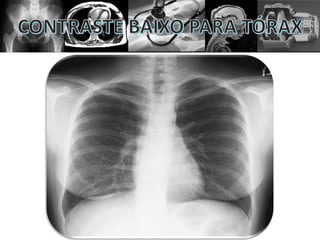

• CONTRASTE ALTO = ESCALA CURTA

• CONTRASTE BAIXO = ESCALA LONGA

• O contraste é a diferenciação dos tecidos;

• O contraste é a absorção diferencial.

Contraste alto ou baixo não significam ser bom

ou ruim por si só. Diferentes estruturas precisam

de determinado tipo de contraste específico.